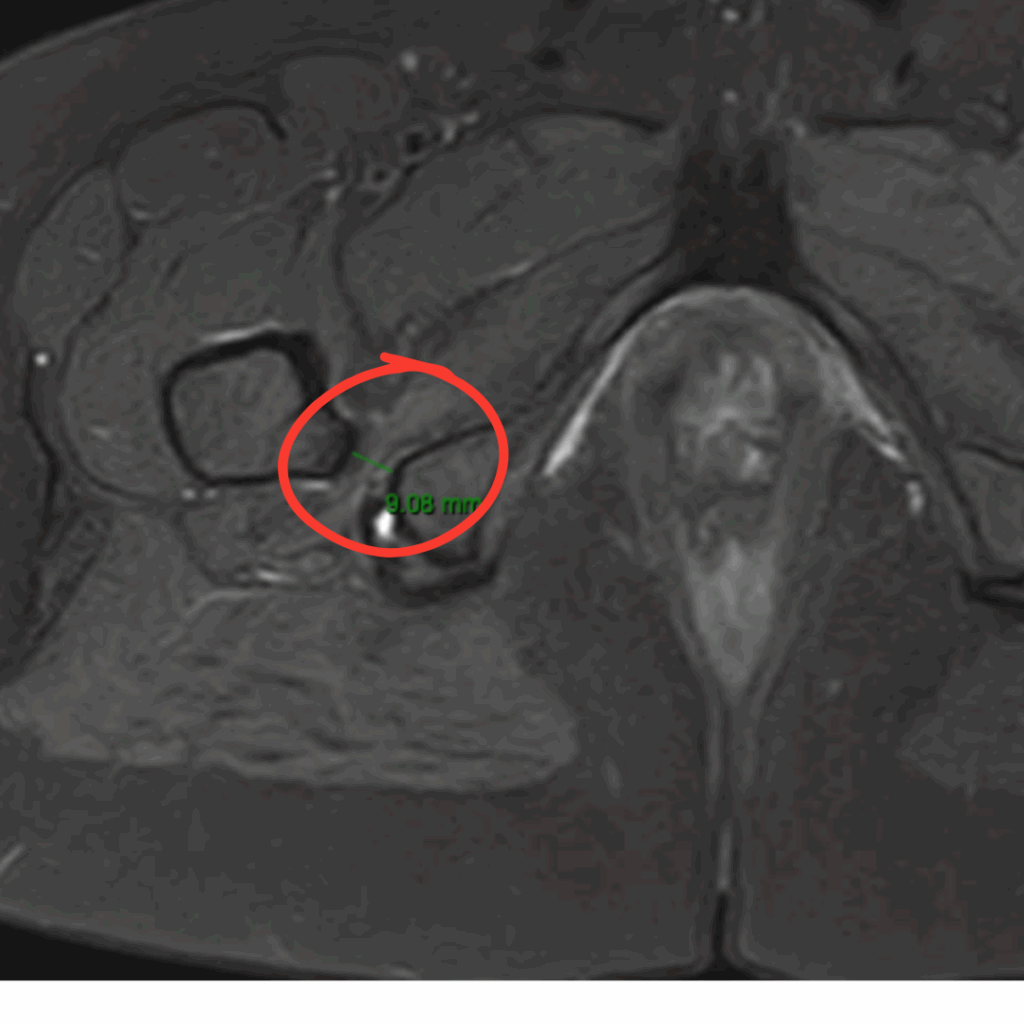

O diagnóstico do impacto isquiofemoral é feito por um especialista em quadril, com base em exame físico e exames de imagem. A ressonância magnética é o exame mais indicado, pois permite avaliar o espaço entre os ossos e o estado do músculo quadrado femoral. Porém, muitas vezes, a ressonância magnética pode vir a apresentar um resultado falso-negativo, ou seja, mesmo com a doença presente ela pode vir normal. Isso ocorre devido a falta de um protocolo especifico para avaliar o impacto isquiofemoral. Por isso a necessidade do ortopedista estar atento ao diagnóstico para poder pedir o exame corretamente.

A medição do espaço isquiofemoral ajuda bastante no diagnóstico e espaços menores que 17mm corroboram bastante quando associados a sintomas clássicos.